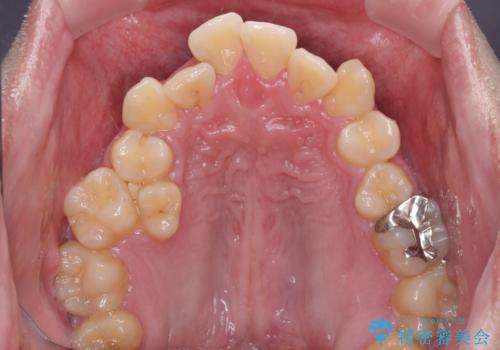

- 八重歯を気にして来院された患者様です。

上下左右の犬歯が八重歯になっており、口元にもやや突出感があるため、上下左右の小臼歯4本を抜歯し、ワイヤー装置にて矯正治療を行うこととしました。

右上第一小臼歯は歯根癒着により移動せず、左上第二小臼歯は移動はするものの非常に動きが鈍かったため、抜歯したスペースを閉じるまでに非常に時間がかかってしまいました。